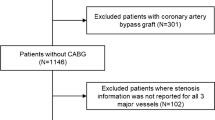

This study included patients suspected to have CAD who underwent both coronary angiography and PET with 15O-labelled water within an interval of 2 months. No clinical events or changes in medication occurred between the two studies. Patients with a history of myocardial infarction (MI) or coronary artery bypass grafting were excluded. This study enrolled 74 patients (53 men and 21 women, mean age 63.0±9.8 years) who matched all the criteria.Seven age-matched normal volunteers served as controls for the MBF and vasodilator measurements. They were selected because their history and physical examinations placed them at low risk for CAD; all had a normal resting electrocardiogram (ECG) and no coronary risk factors.Cardiac medications were not withdrawn before the study because of the severity of anginal symptoms. All patients were carefully instructed to refrain from caffeine intake and smoking during the 24 h before the PET study. All of them gave written informed consent. This study was approved by the Ethics Committee of Hokkaido University Hospital.

Coronary angiography

All patients underwent coronary angiography. Selective angiography of the right and left coronary arteries in multiple views was performed using the Judkins technique. Multiple manual injections of contrast medium were performed. Using the computerised quantitative coronary angiography analysis system (CAASII System; Pie Medical Imaging, The Netherlands), coronary stenosis severity was assessed. Coronary artery stenosis was considered significant when there was a reduction of more than 50% in the diameter of the main branch.